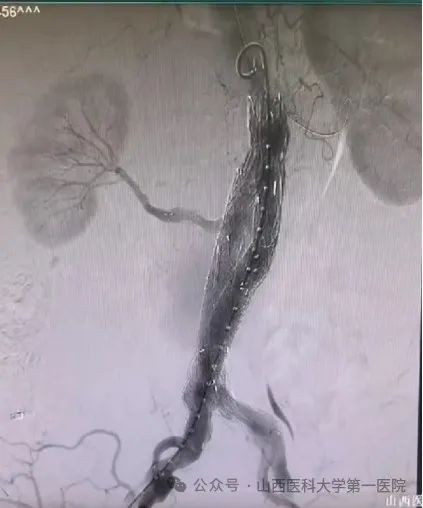

▲图为术后CTA复查,双肾动脉血供正常,腹主动脉覆膜支架内血流正常,无明显内漏。

这种纯腔内治疗腹主动脉瘤并重建双肾动脉的手术难度很高,在国内顶尖医院也属少见。在麻醉科、手术室的通力合作下,患者手术获得成功,术后恢复顺利,经CTA复查双肾动脉血供正常,腹主动脉覆膜支架内血流正常,无明显内漏。